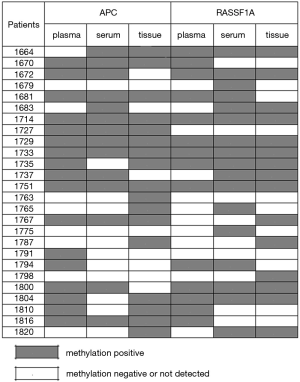

Combination methylation results

Considering the condition of at least one gene methylation of RASSF1A and APC, we got a much higher methylation frequency list in Table 4. For lung cancer patients, we combined three kinds of samples as well as two genes all together and the methylation rate was 88.5%. Among the 26 early stage lung cancer patients, only three patients showed no methylation for both RASSF1A and APC in three different sample types (Figure 4). The coincidence rate of methylation between plasma and serum of the 26 early stage lung cancer patients was 65.4% for RASSF1A and 73.1% for APC. For RASSF1A and APC, the methylation comparation between plasma and biopsy tissue samples both showed a coincidence rate of 57.7%. The coincidence rate between serum and biopsy tissue samples was 65.4% with RASSF1A and 57.7% with APC. As for RASSF1A, twelve patients’ methylation status of biopsy tissue matched the plasma and serum and the coincidence rate attains 46.2%. It displayed the same as for APC. There were eight patients’ positive methylation results in blood did not match their biopsy tissue results for RASSF1A. And for APC, the number is six. Also, three patients’ positive biopsy tissue methylation results did not match their blood's detection results for RASSF1A. And for APC, there were four cases.

In this study, a few cancer patients did not get positive tissue results when their blood tests showed positive. One possible reason was that the tissue here was obtained just by biopsy not by surgery and the biopsy tissues might not 100% represent cancer tissues because of doctors’ medical skills or some other factors. A few pathological reports of biopsy samples just found necrosis tissues could support this point. So the detection of resected tumor tissues could reveal the real methylation status. There remained some other cases whose biopsy tissues were positive methylation but plasma and serum both got negative results. This was probably because all the enrolled cases were early stage lung cancer and the amount of cancer-related methylated TSGs in blood might mainly depend on the tumor size and cancer stage. However, the concordance of methylation in peripheral blood and tumor tissue might be the most valuable evidence in the diagnosis of early stage lung cancer.

In the present study, we used multiple samples including plasma, serum and biopsy tumor tissues not only to improve methylation rate but also aimed to find out a much more suitable sample for DNA methylation detection. Firstly, our results of combined methylation rate of lung cancer patients had been highly improved to 88%. Secondly, methylation comparison of paired samples in lung cancer patients revealed that the methylation rates of the three different sample types were all around 60% and there was no significant difference among plasma, serum and biopsy tumor tissues. So we chose plasma as specimen with advantages of easy collection, minimal invasion and repetitive test.